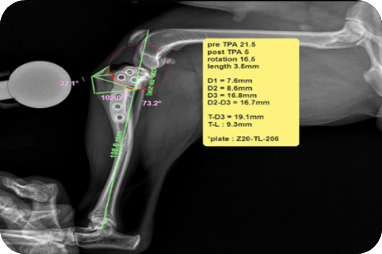

전방십자인대 파열(TPLO)

수술(TPLO)